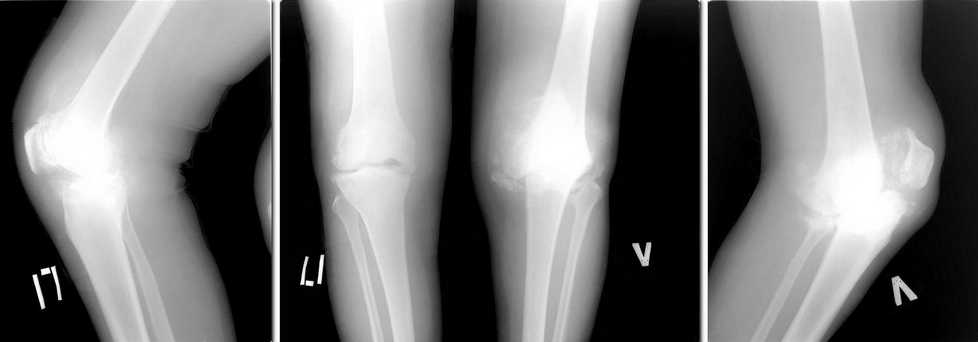

дравствуйте коллеги, возможно кто-то сталкивался с подобной ситуацией. Пациента

беспокоят боли в коленных суставах в течении 5 лет. 1,5 года назад установлен диагноз:

Нейросифилис. Находится на диспансерном наблюдении у венеролога. Обследован онкологом,

фтизиатром "своей" патологии не находят. Бакпосев синовиальной жидкости - нет роста. Боли в

коленях постоянные. Ходить может. Разгибание полное, сгибание 90*. На представленных

рентгенограммах в сравнении с предыдущими, 2 месячной давности (в настоящее время не

располагаю), добавился патологический перелом медиального мыщелка левого бедра. Природа

артроза не ясна, однако, умозрительно - нейросифилис.

Дилемма такова:

1)Эндопротезирование? но беспокоит вопрос о стабильности компонентов протеза в будущем, а

следовательно и целесообразности деяния. 2)Артородезирование? - состоится ли артродез на

фоне продолжающегося разрушения костей. Обе операции тенически вполне выполнимы. И

последнее - следует ли оперировать. Заранее спасибо за добрые советы.